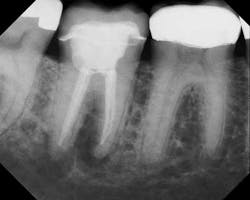

Preop